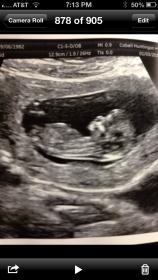

The pic is really small, girly skull?

When I enlarge the pic I see a nub and I would lean girl

The picture is very small however, from what I can make out it does look very girly!!

I would lean girl as well. How many weeks are you?

Yes agree with what others have said. From what I can see, nub looks flat and girly.

Thanks everyone for your guesses. I was 12 weeks and 5 days at this ultrasound.

12 weeks 5 days here. 14 weeks now.